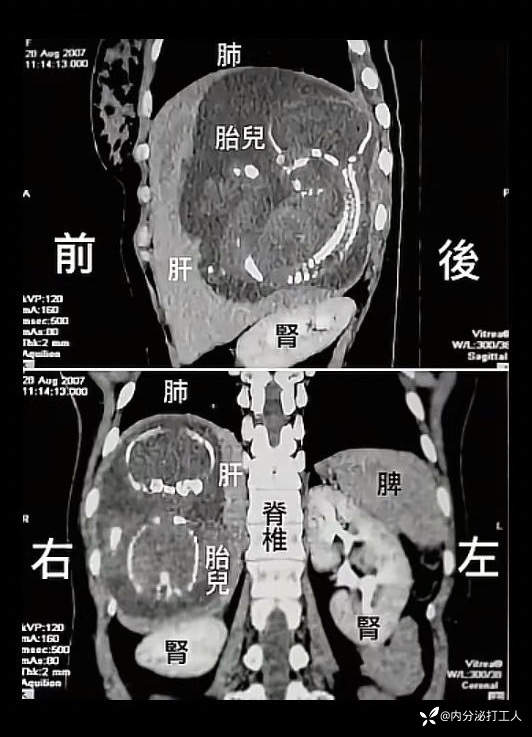

病例一例罕见宫外孕内分泌打工人护士 · 发布于 47 分钟前 · 来自 iOS · IP 湖南湖南69 浏览病例信息转载一例影像,请各位老师检阅医生必看典型病灶图14091 讨论异位妊娠 (149)纠错回复收藏点赞